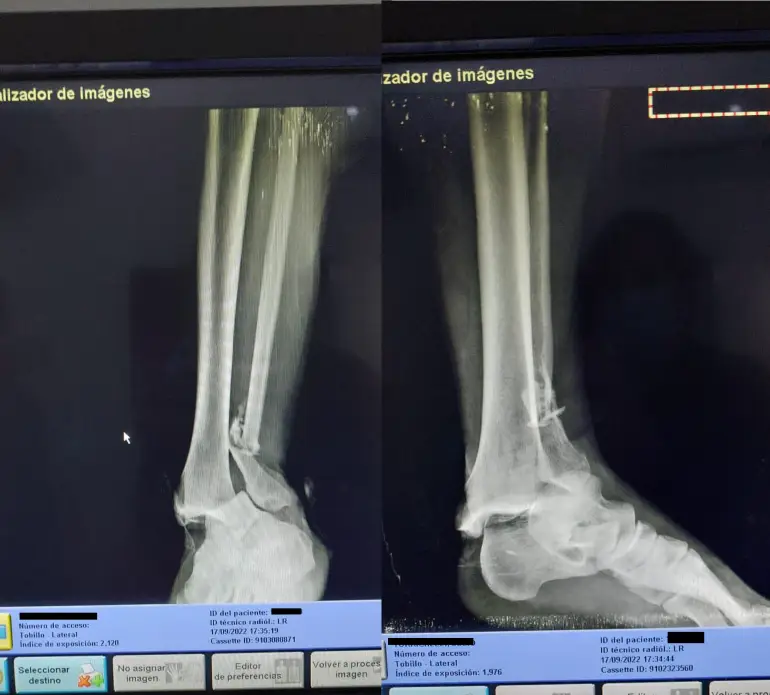

Un jugador terminó internado luego de una terrible patada. Tuvo que ser operado y le colocaron clavos.

Allí se constató que sufrió una fractura expuesta de tibia y peroné. Por eso tuvo que permanecer internado para la colocación de los clavos correspondientes.